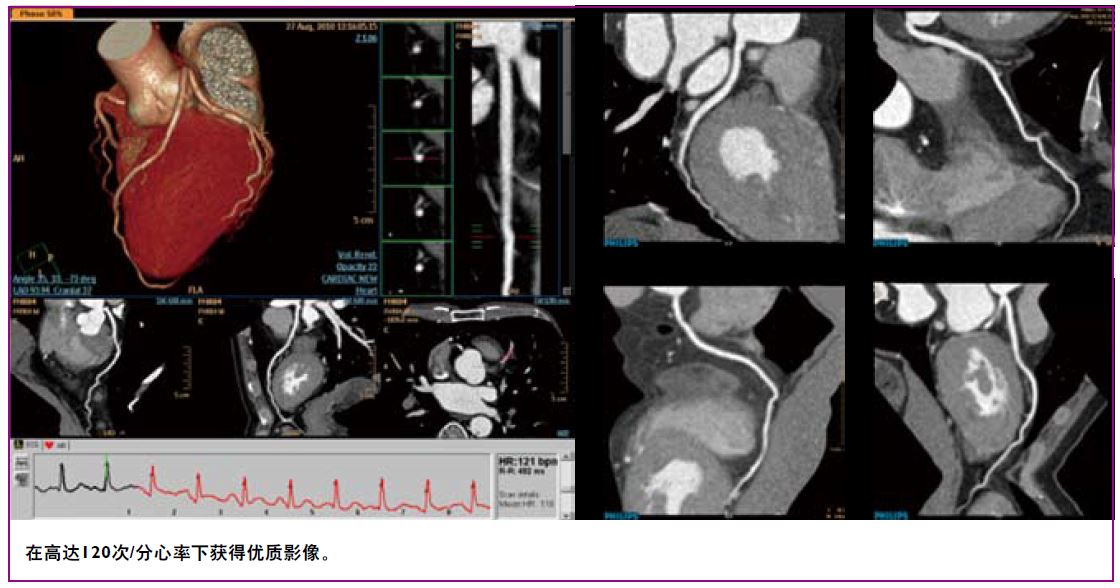

凭借0.27秒/圈极速旋转,8厘米宽体覆盖以及完善的解决方案,极速CT令心脏检查驾轻就熟。